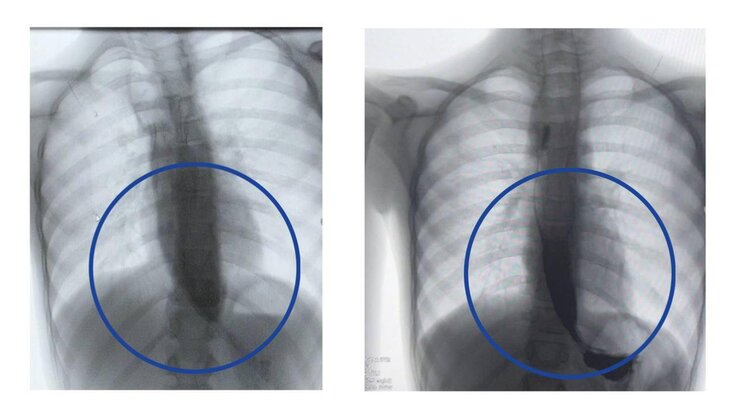

Врачи Детского клинического центра имени Л. М. Рошаля спасли девочку с пятикратным расширением пищевода. Об этом сообщила пресс-служба подмосковного Минздрава.

Девятилетняя девочка поступила в медучреждение с редким заболеванием – ахалазией кардии, из-за которого ее пищевод был расширен почти до 4 сантиметров, когда в норме его диаметр составляет от 7 до 10 миллиметров.

Данная процедура, по его словам, уже доказала свою эффективность у взрослых, однако в детской практике применяется редко. Тем не менее операция прошла успешно, благодаря чему контрастное исследование подтвердило свободное прохождение пищи в желудок уже на следующий день.